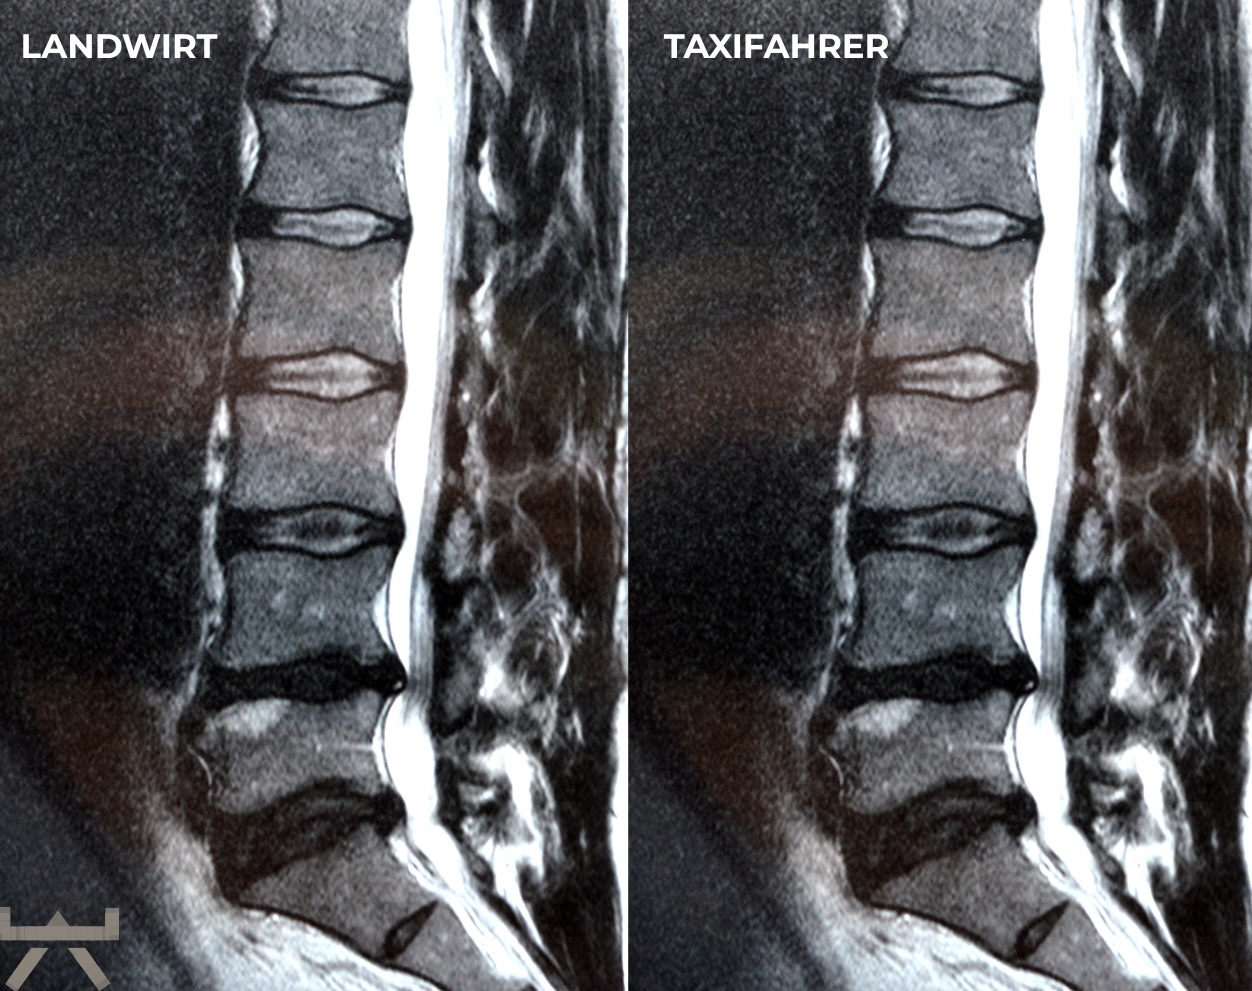

Arthrose wird durch schwere Arbeit verursacht.

Viele machen ihre Arbeit oder ihren Sport für Arthrose verantwortlich, obwohl die meisten Forschungsergebnisse feststellen, dass unsere beruflichen und freizeitlichen Aktivitäten einen relativ geringen Einfluss auf strukturelle Veränderungen haben. Eine der interessantesten Möglichkeiten, dies zu demonstrieren, sind MRT-Studien an schmerzfreien genetisch eineiigen Zwillingen, die aber sehr unterschiedliche berufliche und freizeitliche Aktivitätsniveaus haben, und trotzdem sehr ähnlich aussehende Scans aufweisen. Studien zeigen uns diesbezüglich, dass eine Wirbelsäule, die den größten Teil des Tages sitzt, jener bemerkenswert ähnlichsieht, welche den ganzen Tag schwere Arbeit leisten muss. 11